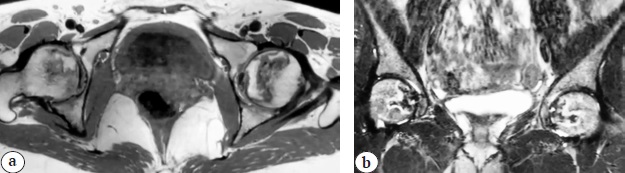

At 75 days after the disease onset, the patient complained of severe pain in the hip and knee joints, hips, and lower back (VAS 8 points) and therefore was forced to use crutches when walking. He consulted a neurologist and was diagnosed with an intervertebral hernia in the lumbar spine. Conservative treatment was recommended for 4 weeks with nonsteroidal anti-inflammatory drugs, muscle relaxants, intravenous infusions with dexamethasone 4 mg in combination with 0.5% novocaine 50 mL three times, vitamin therapy, and physiotherapy. During the therapy, the patient’s condition improved (a decrease in VAS to 4 points), and the patient refused to use crutches and changed them for a cane. During repeated examinations by a neurologist, a hip joint pathology was suspected, which was confirmed by MRI that revealed ARCO IIC bilateral necrosis of the femoral heads (Fig. 2).

Fig. 2. MRI signs of bilateral femoral head osteonecrosis (ARCO IIC) in patient 2: a — axial view; b — frontal view